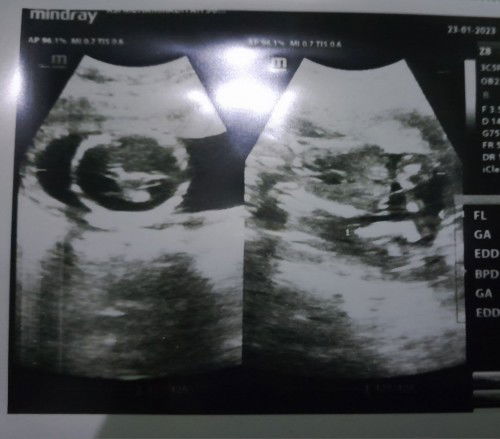

Bunda ijin tanya.. Aku usg di 35w dan bbj rendah cuman 1,8 Di usg umur kehamilanku jadi 33w bund, dan sama bu dokter hplnya jadi diundur juni akhir karena hpl sebelumnya awal juni karena bbj rendah gak sesuai umur kehamilan tapi semuanya normal (seperti ketuban, plasenta, tulang, posisi) kondisi aku juga baik, katanya paling tidak harus ada 2kilo setengah atau 3kilo buat lahiran. Memangnya hpl bisa mundur karena bbj rendah bund? Kira2 kekejar gak ya bbj nya sampai hpl nanti, jadi worry sampai ke bawa mimpi, makan apa ya bund buat mempercepat pertumbuhan bbj? #seriusnanya #bantusharing #ingintahu #firstmom

Numpang cerita ya bunda2. Ini kehamilan pertama aku, umur kehamilan 20w hari ini. Dulu saat kedua kali periksa di kehamilan 13w sama bu dokter di usg, djj nya tidak terdeteksi tapi janin gerak2. Dan hari ini aku habis periksa lagi dan djj nya juga tidak terdeteksi. Perutku membesar, sudah beberapa kali kedutan juga dan idak ada keluhan apa2, cuman kadang nyeri hilang timbul di perut bagian bawah, aku cek di google katanya normal karena peregangan ligamen dan rahim yang mulai mengembang, keluar flek pun juga alhamdulillah tidak pernah dan jangan sampai. Habis periksa bukannya tenang malah jadi kepikiran, rasanya gak tenang kalau belum dengar djjnya :') #bantusharing #firstmom